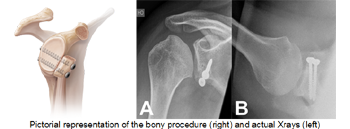

The open operation (latarjet procedure):

Commonly known as a “full reconstruction”has a higher success rate especially in people who have had several dislocation over many years or who are very active and play elite contact sport. The success rate of the open operation is greater than 95%. The open operation is preferable when there has been significant bony damage as it allows for bone grafting procedures to be performed.

It involves a cut in front of the shoulder. The coracoid bone is cut along with its muscle attachments and fixed in front of the glenoid bone to increase the stability of the shoulder and prevent the ball from dislocating.